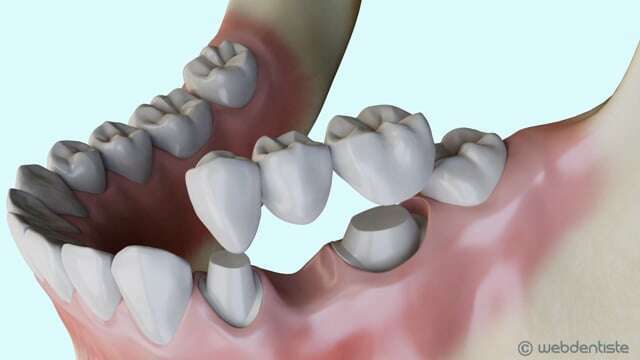

Traitement d'une carie par inlay/onlay